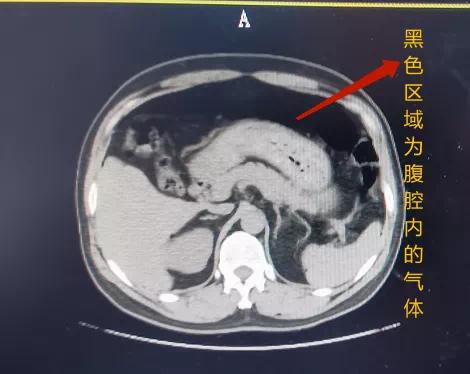

高压气枪对人造成的伤害

首先就是 肚子胀气

可看到这些受害者的身体

被吹成随时可能炸开的气球

内脏器官更好不到哪儿去

有些受害者的 大小肠

就因为经不住迅猛的气压

被打成了千疮百孔的竹荪状

高压气体一旦进入人体

首先遭殃的就是 直肠、结肠、盲肠

可 正常厚度也只有 1-4mm